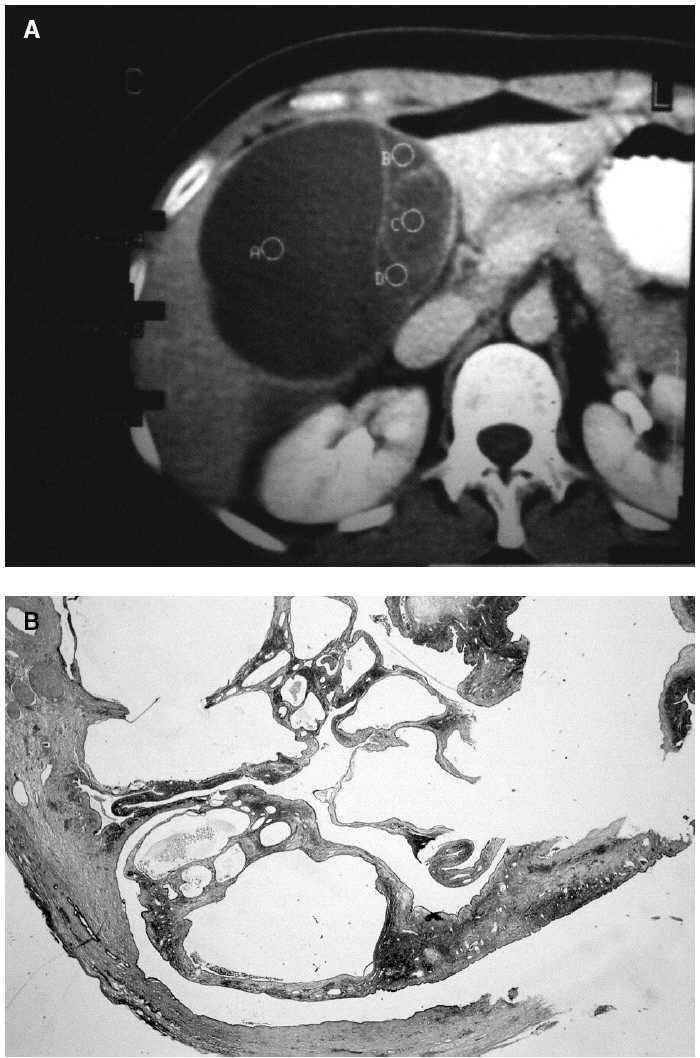

Fig. 1 A: tomografía computarizada abdominal, corte axial. Puede observarse la presencia de una tumoración quística de 12 cm en su diámetro mayor, localizada en el segmento IV hepático, de paredes finas, y que se encuentra trabeculada por la existencia de finos septos intraquísticos. B: detalle histológico del cistoadenoma seroso, que está constituido por múltiples quistes de diámetro variable, delimitados por septos finos (hematoxilina-eosina, ×1,25).

Mujer de 40 años sin antecedentes de interés que consultó por dolor en el hipocondrio derecho de 1 mes de evolución sin acompañarse de náuseas, fiebre, ictericia, coluria u otros síntomas. A la exploración destacaba hepatomegalia dolorosa de dos traveses de dedo. Los datos analíticos de laboratorio se encontraban dentro de límites normales a excepción de un discreto aumento de la gammaglutamiltranspeptidasa (GGT) (45 U/l). La ecografía abdominal describió una masa quística bien delimitada de 10 × 12 cm de diámetro en el lóbulo hepático derecho, con septos en su interior y alguna imagen nodular en su pared. La tomografía computarizada confirmó los hallazgos de la ecografía y mostró que no afectaba a estructuras vasculares o biliares adyacentes (fig. 1). La serología hidatídica fue negativa. Se intervino quirúrgicamente a la paciente mediante una laparotomía subcostal derecha ampliada, y se observó una lesión situada en el segmento IV hepático, de superficie lisa y blanquecina. Se obtuvo muestra por punción del contenido del quiste, un líquido seroso, amarillento y acelular. El análisis citológico y la biopsia intraoperatoria no demostraron signos de malignidad. Se practicó una enucleación completa de la lesión y colecistectomía añadida. El informe anatomopatológico definitivo describió una tumoración multiquística, revestida por epitelio cúbico simple en algunas áreas y cilíndrico simple en otras, débilmente positivo con la técnica de PAS y de ácido peryódico-Schiff (PAS) características benignas, por lo que el diagnóstico final fue "cistoadenoma seroso". El postoperatorio transcurrió sin incidencias. Tras 7 años de seguimiento la paciente permanece asintomática y sin signos radiológicos de recidiva.